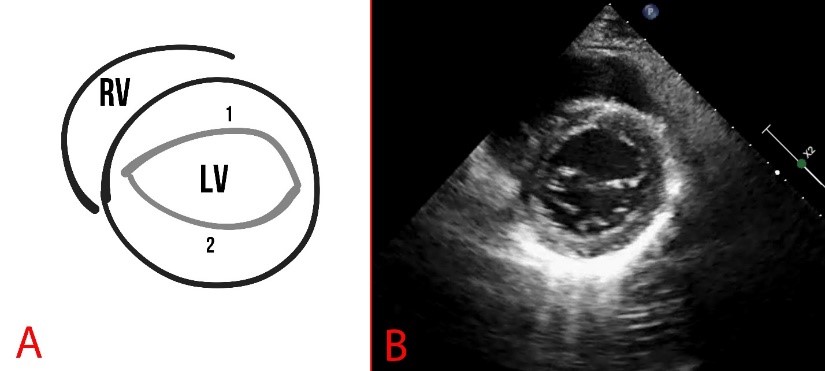

The anterior leaflet of the mitral valve is larger than the posterior mitral leaflet and more mobile. MVP is assessed during systole (at the moment the valves close) and is considered true when a prolapse is registered in two or more views (Figs. 5,6).

Fig. 6. Schematic representation (A) and echocardiography (B) of normal findings in parasternal long-axis view. The dotted line indicates the mitral annulus, and numbers 1,2 indicate the leaflets of the MV. AO, aorta.